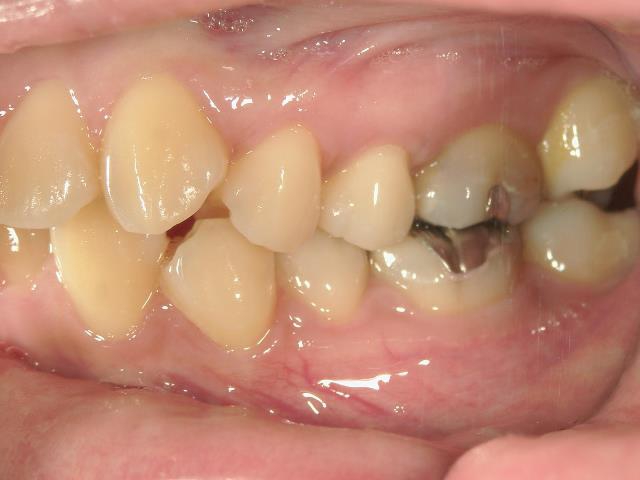

矯正歯科 治療前

矯正歯科(全顎ワイヤー矯正)治療後

全顎ワイヤー矯正 症例(7

)

28歳女性 浜松市西

区在住

治療期間3

年11ヶ月